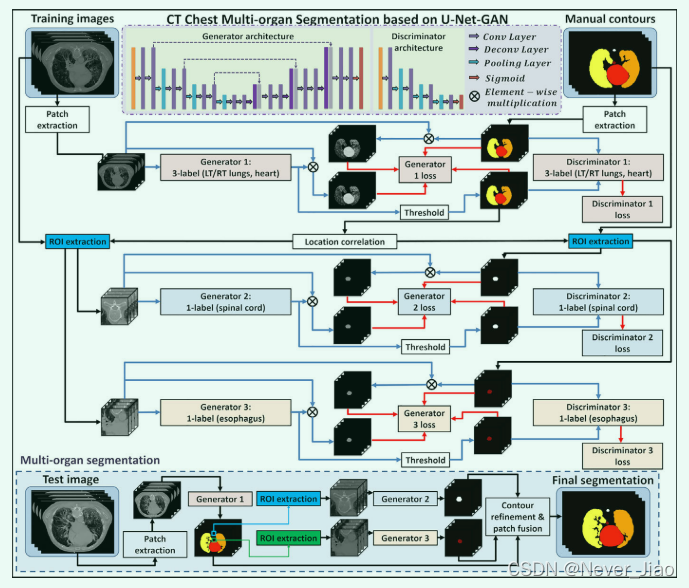

提出的多个 OAR 的分割算法由训练阶段和分割阶段组成。 图 1 概述了我们的分割方法的工作流程示意图。 对于给定的一组胸部 CT 图像及其相应的手动分割的 OAR,包括心脏、左肺、右肺、脊髓和食道,手动轮廓被用作胸部 CT 图像的深度学习目标。由于脊髓和食道比心脏和肺小得多,因此仅使用一种分割模型很难同时分割所有轮廓。 为了解决这个问题,我们首先训练一个基于三标签的分割模型来同时分割心脏、左肺和右肺。 分割模型的每个标签代表一个参考区域。 分割模型由一个 2.5D 端到端的基于patch的 GAN 模型实现,该模型以四个连续的 CT 图像切片作为输入patch,即补丁大小为 512×512×4,并输出相等的 大小的心脏、左肺和右肺分割。食管和脊髓分割分别在裁剪的感兴趣区域(ROI)patch上进行训练。这些ROI是根据食道和脊髓与肺的相对位置获得的。我们首先定位包含肺总体积最大的切片,并将食管ROI的中心设为总肺的质心(所有点的平均位置)。同样,将脊髓ROI的中心设为同一切片上左肺和右肺最后两个点的中点。ROI大小设置为64×64 ,以确保食道或脊髓包含在所有CT切片的裁剪区域中,作为ROI提取的第一个网络的解剖异常值或潜在错误的缓冲。用于食管和脊髓分割的 3D GAN 模型采用相同的架构,以 64×64×64 个 CT patch作为输入和输出等大小的二进制分割。对于 2.5 D 和 3D GAN 模型,输入patch都是通过步长为1×1×2的patch裁剪获得的,即每两个相邻的块有两个重叠的切片。

在分割阶段,首先从新的CT图像中提取由四个连续切片组成的patch,并将其送入第一分割模型中,以获得心脏,左肺和右肺轮廓。然后,根据第一个模型生成的肺轮廓裁剪食道和脊髓的ROIs。将3D ROIpatch输入训练有素的第二和第三分割模型中,分别获得端到端食道和脊髓轮廓分割。最后,所有分割都根据原始CTpatch的空间信息确定了各自的位置。通过patch融合重建OAR轮廓,并通过轮廓细化 (例如填充孔,侵蚀和扩张操作) 进行细化。

Fig.1 提出的胸部计算机断层扫描 (CT) 多器官分割算法的示意性流程图。上部 (白色) 显示了所提出方法的训练阶段,该阶段由三个生成对抗网络 (GAN) 组成。下部 (浅蓝色) 显示分割阶段。在分割阶段,将CT切片送入三个训练有素的模型中,以进行危险器官分割。[彩色图形可在wileyonlinelibrary.c om查看]

所提出的 GAN 模型的细节如下所示。 CT patch被输入生成器网络 U-Net,以获得端到端的分割轮廓。如图 1 的生成器架构部分所示,生成器网络由压缩路径(左侧)、解压缩路径(右侧)和连接这两条路径的桥接路径(中间)组成。压缩路径由两个卷积层和一个池化层组成,以降低分辨率。在每个卷积层中,可以通过 3D 卷积提取特征表示,然后是参数整流线性单元 (PReLU)。解压路径由两个卷积层和一个反卷积层构成,以提高分辨率。解压路径与压缩路径的结构类似,只是压缩路径没有跨步卷积。解压缩路径使用桥接路径来连接来自相同大小的压缩和解压缩路径的特征。具有这种拼接的 U-Net,即密集块网络,鼓励每条路径同时获得高频信息(如纹理信息)和低频信息(如结构信息)来表示图像块。== 为了输出相等大小的分割轮廓概率图,使用了 2×2×2 步长的反卷积。 在生成器的最后,使用 soft-max 算子生成轮廓的概率图==。阈值用于将概率图二值化为轮廓的二进制掩码,称为生成的轮廓。 然后,如鉴别器架构部分所示,鉴别器用于判断生成的轮廓与参考手动轮廓的真实性。 判别器是一个典型的基于分类的 FCN,它由几个卷积层组成,每个卷积层后面跟着一个池化层。 鉴别器输出一个 1×1×1 的变量,其中 1 表示真,0 表示假。